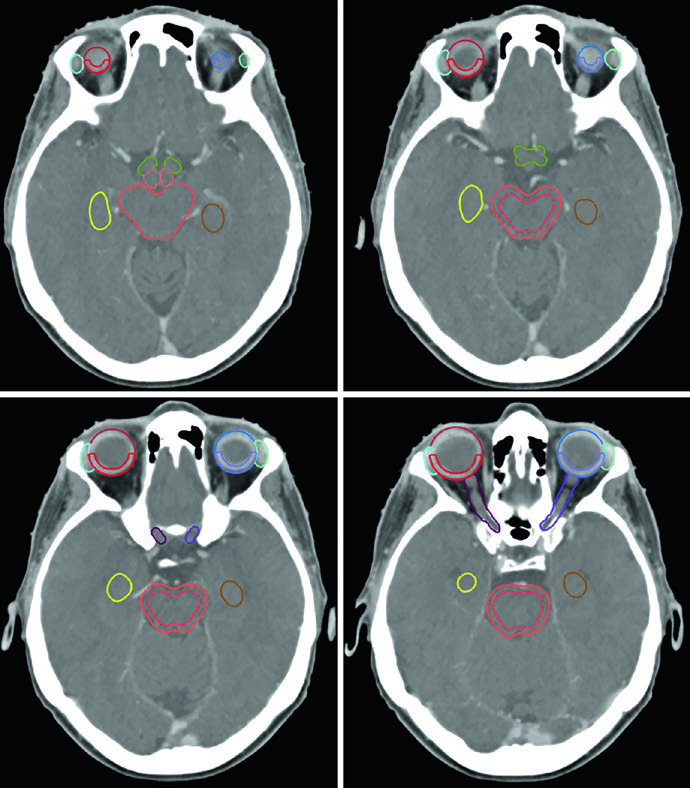

A lista de estruturas normais a contornar é extensa e reflete a sensibilidade das estruturas vizinhas. Para a maioria dos tumores benignos do SNC, o conjunto de OARs inclui: encéfalo total, encéfalo não envolvido (encéfalo menos GTV ou CTV), tronco encefálico dividido em core e superfície (rind de 3 mm), medula espinhal, cócleas direita e esquerda, globos oculares, cristalinos, nervos ópticos, quiasma, retinas, glândulas lacrimais, lobos temporais, hipocampos e hipotálamo. Volumes de risco planejado (PRVs) podem ser criados para tumores adjacentes a estruturas críticas, auxiliando na dosimetria e na avaliação do plano.

Cada OAR tem uma janela de visualização preferida. O tronco encefálico, quiasma óptico e componentes intracranianos dos nervos ópticos são melhor visualizados em janela cerebral. Os nervos ópticos nos canais ópticos e seus componentes orbitários ficam mais nítidos em janela de partes moles. As cócleas, por sua vez, só são identificadas com precisão em janela óssea. Já o hipocampo — especificamente a zona subgranular — é delineado em T1 de RM e visualizado na TC como substância cinzenta hipointensa, do nível do esplênio do corpo caloso superiormente até a extensão inferior do corno temporal do ventrículo lateral.

Um ponto prático crucial: a avaliação da TC é essencial para decidir se alterações periosteais e ósseas devem ser incluídas no GTV. No exemplo do meningioma do seio cavernoso (Figura 29.7), o tumor foi delineado com RM de planejamento, recebeu margem de 2 mm para o PTV e foi tratado a 52,2 Gy em 29 frações. As linhas de isodose mostram conformação apertada ao redor do tronco encefálico, quiasma, nervos cranianos adjacentes, artéria carótida e cóclea.

Meningiomas volumosos selares e suprasselares com ressecção incompleta — como na Figura 29.8 — podem requerer expansão de PTV de 3 mm por causa da doença residual extensa. A relação íntima com os globos e o tronco encefálico exige planejamento dosimétrico cuidadoso, frequentemente com IMRT ou VMAT para conformar a dose e proteger essas estruturas.